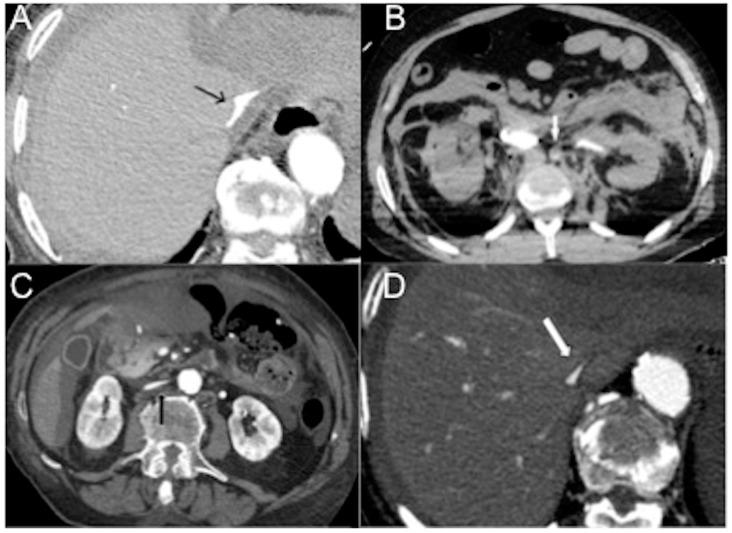

A severe mismatch between the supply and demand of oxygen is the common sequela of all types of shock, which present a mortality of up to 80%. Various organs play a protective role in shock and contribute to whole-body homeostasis. The ever-increasing number of multidetector CT examinations in severely ill and sometimes unstable patients leads to more frequently encountered findings leading to imminent death, together called "hypovolemic shock complex". Features on CT include dense opacification of the right heart and major systemic veins, venous layering of contrast material and blood, densely opacified parenchyma in the right hepatic lobe, decreased enhancement of the abdominal organ, a dense pulmonary artery, contrast pooling in dependent lungs, and contrast stasis in pulmonary veins. These findings are biomarkers and prognostic indicators of paramount importance which stratify risk and improve patient outcomes. In this review, we illustrate the various CT patterns in shock and review the spectrum and prognostic significance of thoraco-abdominal vascular and visceral alarming signs of impending death with the intention of increasing awareness among radiologists and radiographers to prepare for immediate resuscitation when required.

氧供需严重不匹配是各类休克的常见后遗症,其死亡率高达80%。各种器官在休克中发挥保护作用并有助于维持全身内环境稳定。在重症且有时不稳定的患者中,多排CT检查数量不断增加,导致更多常出现的即将死亡的影像学表现,统称为“低血容量性休克综合征”。CT表现包括右心和主要体静脉致密强化、对比剂与血液的静脉分层、右肝叶实质致密强化、腹部器官强化减弱、肺动脉致密、下垂肺野对比剂积聚以及肺静脉对比剂滞留。这些表现是极其重要的生物标志物和预后指标,可对风险进行分层并改善患者预后。在本综述中,我们阐述了休克中的各种CT表现模式,并回顾了胸腹部血管及内脏即将死亡的警示征象的范围和预后意义,旨在提高放射科医生和放射技师的认识,以便在需要时为立即复苏做好准备。